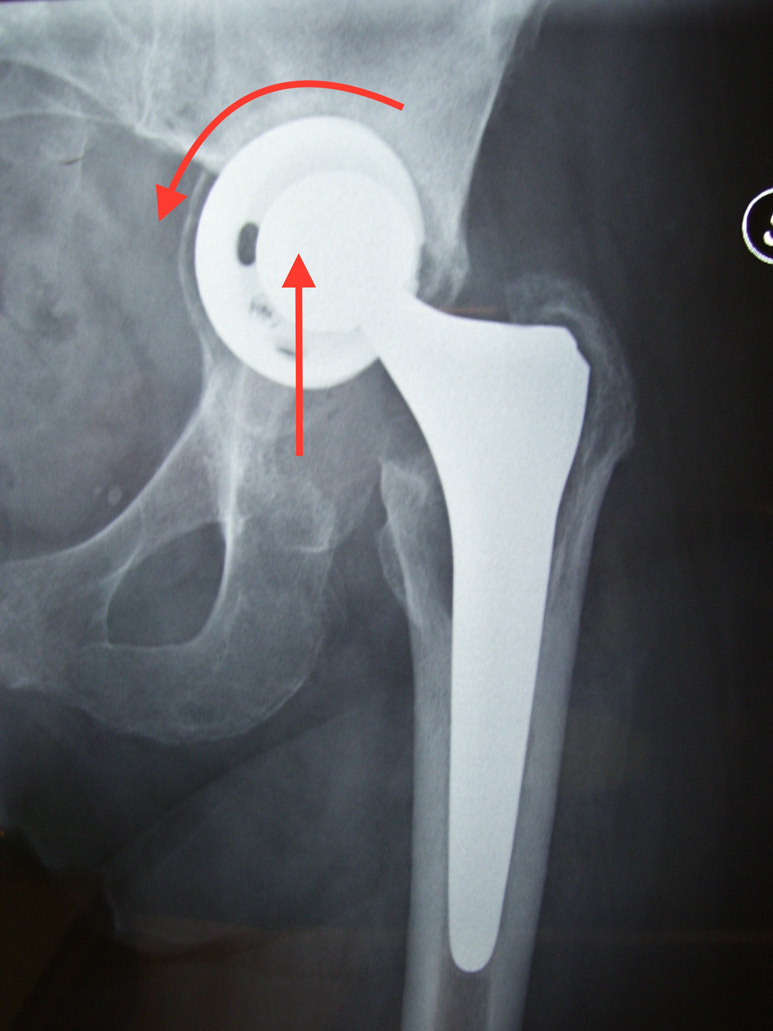

Fig. 1 Paziente con protesi di anca destra operata già 3 volte ( a causa di un’infezione) 10 anni prima. A sinistra protesi di primo impianto operata 3 anni prima.Il cotile è mobilizzato.L’inserto in polietilene (plastica) è usurato e la testa femorale è risalita: la polvere di polietilene dovuta all’usura, entra nell’interfaccia tra protesi e osso ed è causa della cosddetta “malattia da polietilene” che è responsabile dell’ usura dell’osso e dello scollamento della protesi.Nel caso in questione l’usura del femore ha causato un assottigliamento delle corticali così grave che esse presentano un aspetto a guscio d’uovo. La parte terminale della protesi invece è incarcerata e necessiterà, nel corso del reintervento, dell’ apertura (“a panino”) del femore per poter posizionare la protesi definitiva.Si vedono ancora i mezzi metallici utilizzati nel primo intervento, probabilmente per una frattura del gran trocantere.In sovrapposizione si vede il disegno della nuova protesi che verrà impiantata.

Fig.2 Radiografia postoperatoria. I cerchiaggi e la placca sono stati utilizzati per richiudere il femore dopo che esso è stato “aperto” per rimuovere la protesi. Una volta chiuso il femore, si procede al posizionamento dello stelo protesico lungo che deve far presa sulla porzione di femore sano. E’ stato ovviamente cambiato anche il cotile. Trattasi di intervento assai impegnativo.